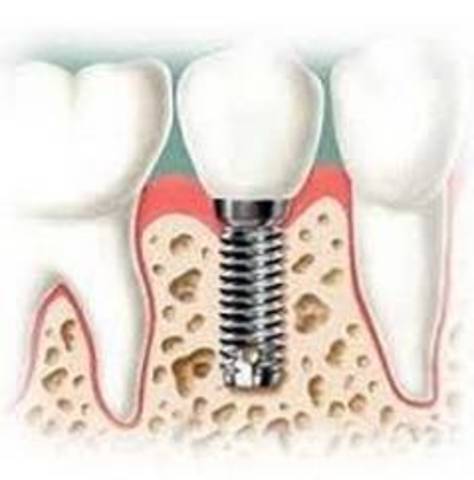

Primera prótesis de titanio en laringe. Los biomateriales y el titanio sólido y poroso utilizados en la prótesis tenían la capacidad de incorporarse a los tejidos de la garganta y convertirse en parte integral.